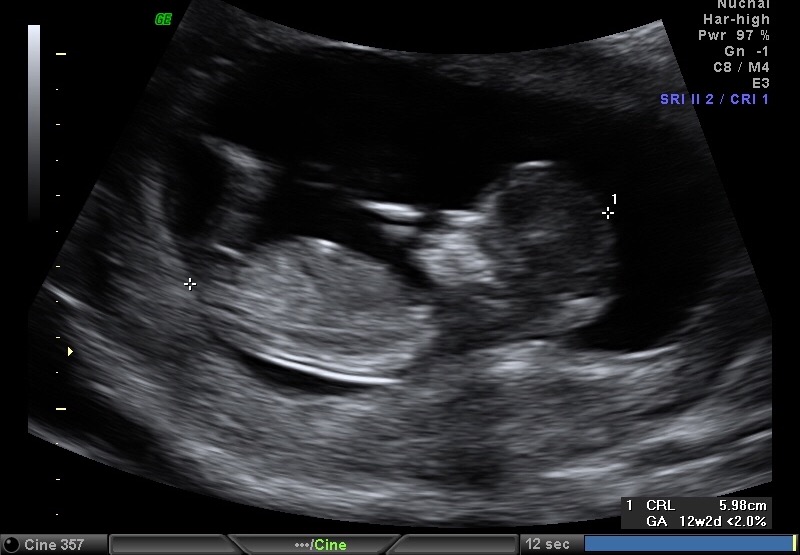

I would really appreciate it if you would take a look at my photos from my NT scan - baby was measuring 12w2d-12w3d.

Attachment 30264

Attachment 30263

Attachment 30265